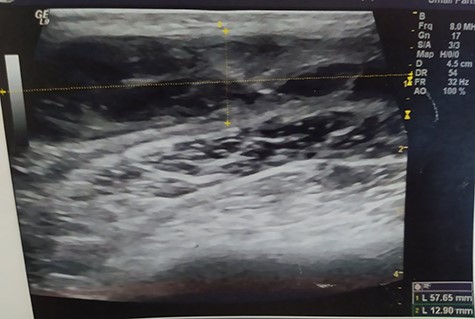

A 55-year-old Caucasian male proceeded to our institution complaining about irreducible swelling of the right iliac fossa and constant discomfort, over the course of a year. His medical history revealed that he slapped against a blunt surface of a furniture a year ago and injured his right groin and pelvis. Due to the accident and the subsequent painful swelling, the patient underwent immediately a pelvic ultrasound the detected an acute hematoma with a diameter of 52 mm into the fatty tissue of the right pelvic fossa (Fig. 1). Ten months after the accident, due to the irreducible swelling, the patient underwent another ultrasound revealing a nonorganized hematoma with thrombotic features (sized as 25 × 60 × 58 mm) (Fig. 2).

Pelvic ultrasound indicating an acute/nonorganized hematoma into the fatty tissue of the right iliac fossa, with thrombotic features.